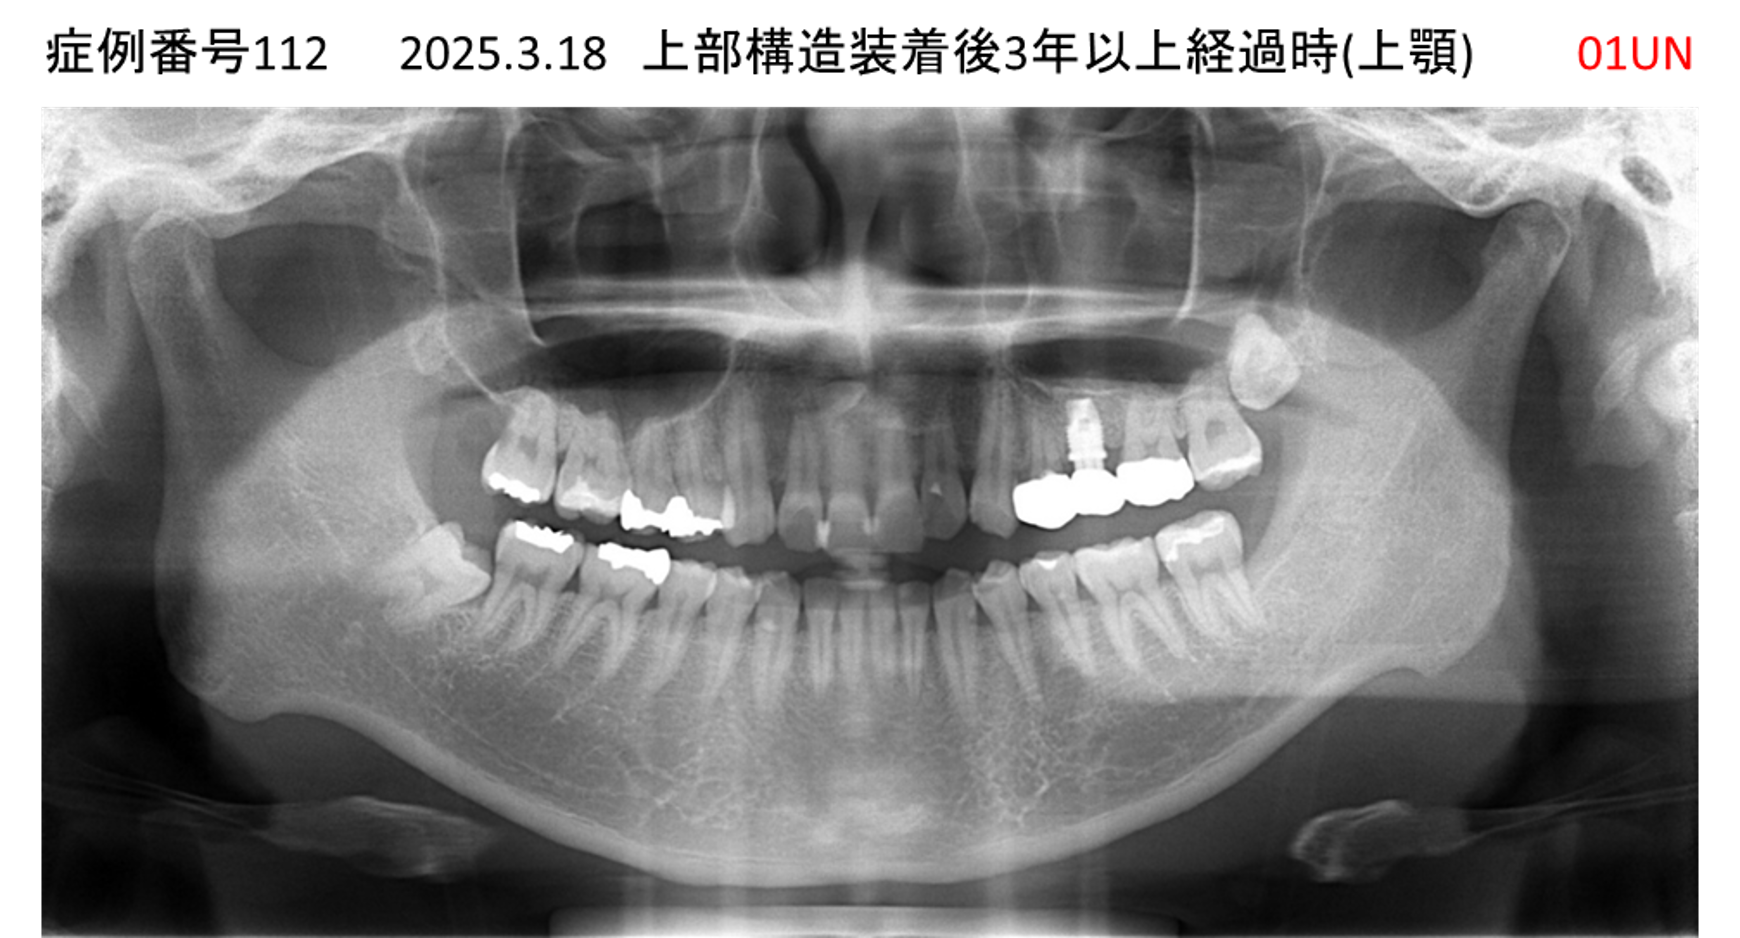

上の前歯が揺れてきてかめない患者様のインプラント症例

| 治療名称 |

インプラント |

| 治療費用 |

335万円+税 |

| 治療期間 |

4か月 |

| 患者さんの症状(主訴) |

上の前歯が揺れてきて噛めない |

| 治療内容 |

サイナスリフト 抜歯即時インプラント |

| 治療結果 |

ちゃんと噛めるようになった。不安がなくなった。見た目がとても良くなったのすごくうれしい。 |

| 治療の注意点(リスク/副作用) |

インプラントが壊れたら再治療が必要 |